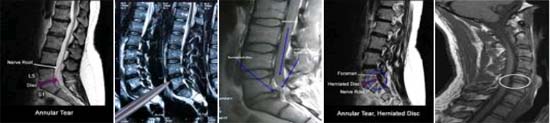

Chẩn đoán thoát vị đĩa đệm không phải dễ dàng. Trên thực tế bệnh hay bị chẩn đoán nhầm với nhiều bệnh khác. Đó là do các triệu chứng lâm sàng chỉ có tính chất gợi ý, để chẩn đoán xác định cần phải làm các xét nghiệm cận lâm sàng và chẩn đoán hình ảnh hiện đại, tốn kém mà không phải bệnh nhân nào cũng có điều kiện để làm. Chụp X-quang cột sống thông thường ít có giá trị, không phát hiện được thoát vị đĩa đệm vì tổn thương đĩa đệm không cản quang, do đó không thấy được trên phim, chỉ gián tiếp đánh giá tổn thương đĩa đệm khi thấy giảm chiều cao khe liên đốt sống, vẹo cột sống. Để “nhìn thấy” đĩa đệm bị tổn thương và thoát vị, phải chụp bao rễ cản quang, chụp cắt lớp vi tính CT, cộng hưởng từ hạt nhân (MRI). Khi đó đĩa đệm được cắt thành từng lát,phân tích hình ảnh rõ ràng và chi tiết. Qua đó người ta có thể đánh giá được hình thái, tính chất tổn thương đĩa đệm, vị trí thoát vị vào ống sống hay vào lỗ liên hợp, cũng như mức độ hẹp ống sống do thoát vị đĩa đệm gây ra. Từ đó bác sĩ lập ra kế hoạch để quyết định các biện pháp điều trị hợp lý.

­ !important;Chỉ định cận lâm sàng và thăm dò chức năng: dau khi bác sĩ biết rõ hoặc nghi ngờ nguồn gốc cơn đau, sẽ được chỉ định chụp cắt lớp hay chụp cộng hưởng từ để khẳng định tổn thương. Các bước chụp và khảo sát ấy sẽ hỗ trợ làm rõ vấn đề như vị trí của đĩa đệm bị thoát vị hay rễ thần kinh vị chèn ép;

­ !important;Hình ảnh chụp X-quang, CT hay MRI có thể chỉ ra đĩa đệm thoát vị, thần kinh bị chèn ép, trượt đĩa đệm, rách đĩa đệm nhưng không nói lên đầy đủ nguồn gốc cơn đau. Các bác sĩ chuyên khoa cột sống còn phải tiến hành tìm hiểu các triệu chứng đặc biệt của bệnh nhân và các khám nghiệm vật lý mới có thể kết luận nguyên do đau;